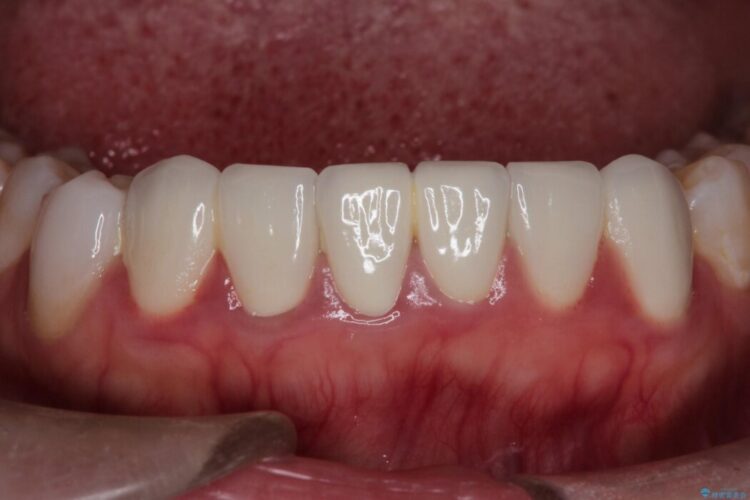

再根管治療とオールセラミックで前歯の気になる変色を解消

再根管治療とオールセラミックで前歯の気になる変色を解消 ビフォー 再根管治療とオールセラミックで前歯の気になる変色を解消 アフター

他院で神経を取った前歯が変色してきたとご相談にいらした患者様です。